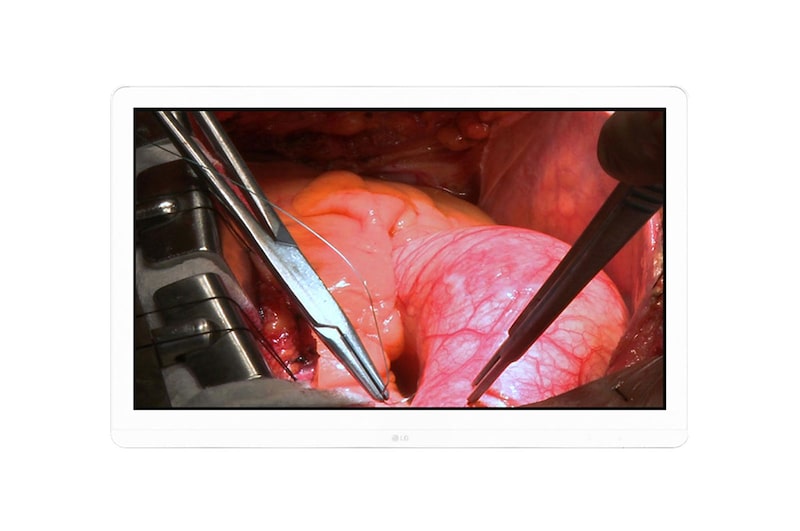

Monitor Quirúrgico 8MP